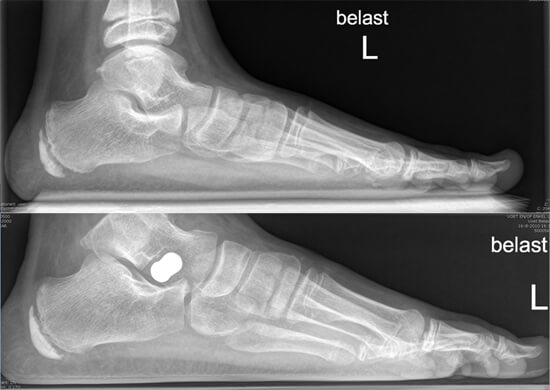

Röntgenfoto voor (boven) en 4 weken na (onder) een arthroereisis operatie

Bij deze operatie plaatst de specialist via twee kleine gaatjes een klein plugje in de holte bij het onderste spronggewricht (zie afbeelding A en B). Dit is het gewricht tussen het hielbeen en het sprongbeen, en zorgt ervoor dat de voet naar binnen en buiten kan kantelen. Door het plugje kan de voet nog normaal bewegen, maar niet meer zo extreem ver naar binnen kantelen. Na de operatie is direct te zien dat de stand van de voet verbeterd is.

Arthroereisis wordt meestal gedaan bij jonge kinderen (8-10 jaar), bij wie de voeten nog in de groei zijn. Het plugje wordt over het algemeen na 2 jaar weer verwijderd, wanneer de voet volgroeid is. De voet stopt namelijk al eerder met groeien dan de rest van het lichaam. Bij jonge kinderen is arthroereisis vaak voldoende om de stand van de voet te verbeteren, soms is ook een achillespeesverlenging nodig, en/of een versteviging van de ligamenten in de voetboog.